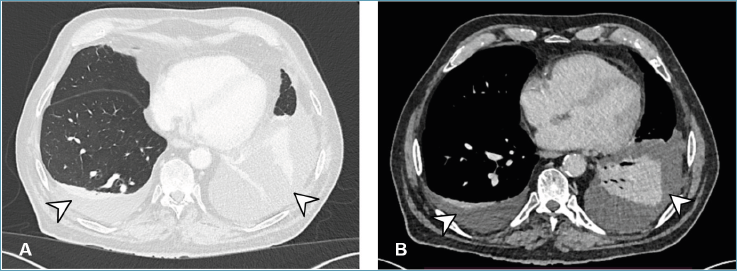

La tomografia computerizzata (TC) toraco-addominale, richiesta per approfondimento, evidenziava la presenza di un versamento pleurico bilaterale con spessore massimo di 28 mm a destra e di 148 mm a sinistra in assenza di franchi ispessimenti pleurici, ma con significativa impregnazione contrastografica della pleura diaframmatica sinistra (Fig. 1). Inoltre, veniva segnalata la presenza di linfoadenomegalie di diametro pari a 12 mm a livello della stazione 4R e di 11 mm a livello della 11R. Nelle scansioni per parenchima polmonare si osservava un’atelettasia del lobo inferiore sinistro e alterazioni disventilatorie della superficie posteriore del lobo polmonare inferiore destro e del lobo polmonare superiore sinistro.

Figura 1.TAC torace, sezioni assiali. Versamento pleurico bilaterale con atelettasia lobare inferiore sinistra (freccia).